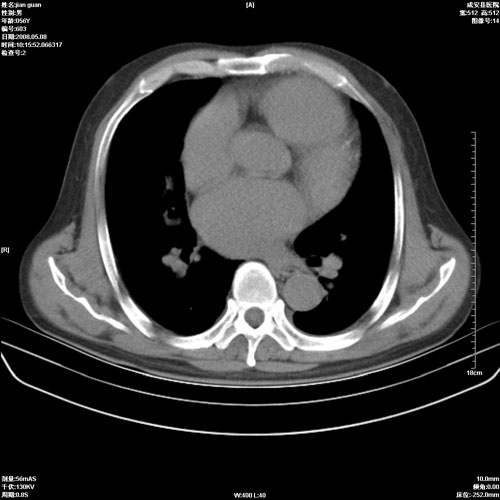

病人 男 60岁 主诉 胸闷 无明显发热 一般情况尚可。

考虑1心功不全,肺水肿

2右上肺结核纤维性病灶、肺气肿

1.右上肺陈旧性肺结核.

2.心脏增大(以左心室增大为著),请结合b超及听诊.

1.两上肺陈旧性结核;慢支肺气肿。

2.肺门血管扩张,心脏增大,为肺心病

考虑.两上肺陈旧性结核;慢支肺气肿。肺心病

1.陈旧肺结核;

2.慢支肺气肿;

3.肺心病.

陈旧性肺结核,左心房扩大,左心衰竭